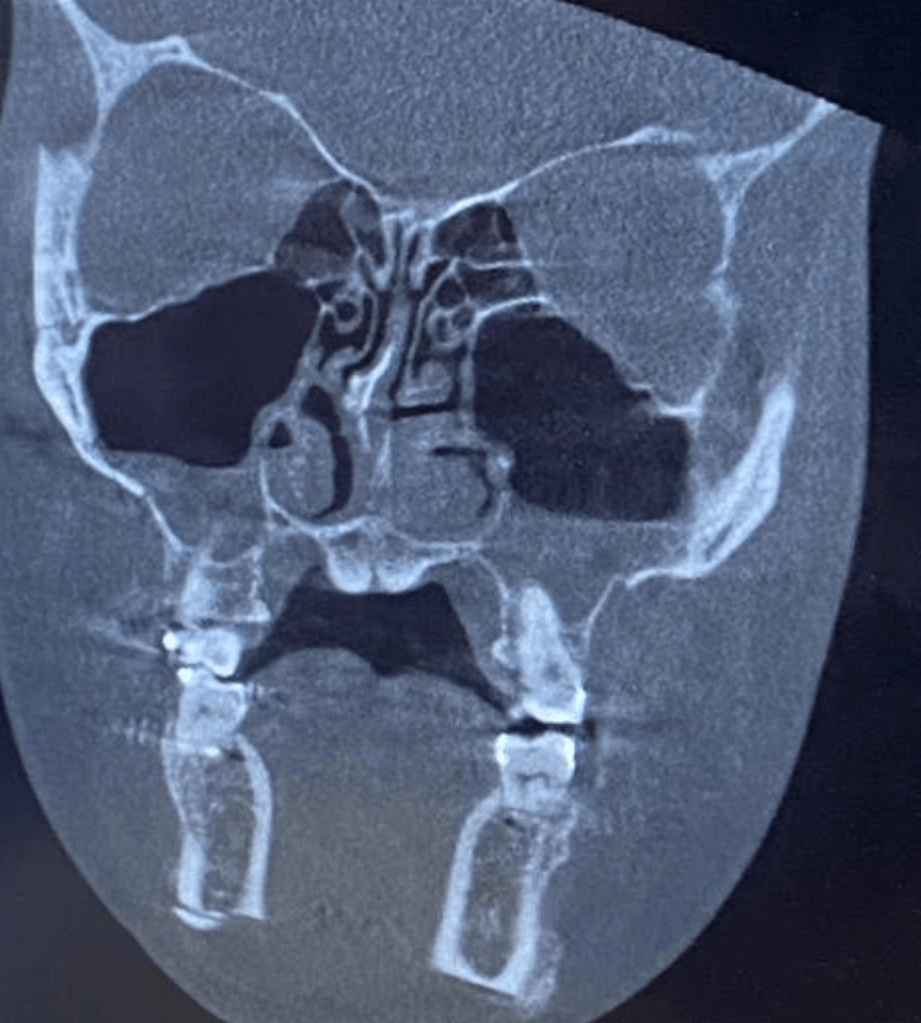

Deviated Septum

My septum deviated within the first hour sometime after my jaw surgery (possibly from intubation removal, a 6.5 mm tube was used to try and avoid deviations like this), and my nose doctor believes it is also broken as well. Most likely “bend beyond repair”, so I will probably need an autologous rib graft but he doesn’t know for sure until he opens up my nose. I really hope he can use my existing septal cartilage, but “expect the worst and you aren’t disappointed” is what I joke with my family about. I am really thankful that there is a solution to this, my septum feels unstable/ the base is off the vomer bone and leaning into one nostril and just feels very awful on top of the issues with breathing that I have been experiencing.